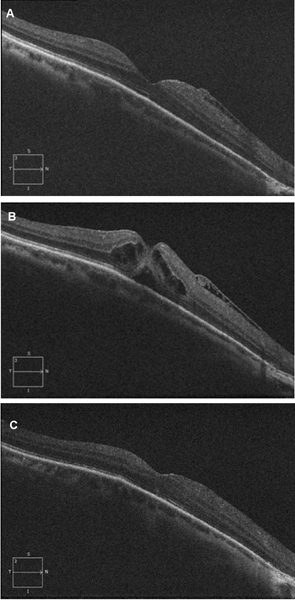

Cierre espontáneo

Es posible observar el cierre espontáneo en un 50% de las tracciones vitreomaculares con agujeros maculares incompletos (grado I en la antigua clasificación por OCT)

11 (

Figura 9), pero sólo se consigue la resolución espontánea en un 2% a un 4% de los agujeros de grosor completo (grados 2-4 de la antigua clasificación)

11,12.

Figura 9. Cierre espontáneo de agujero macular de grosor incompleto y tracción vitreomacular. Se objetiva un agujero que implica las capas externas de la retina, aunque no llega a ser completo en las capas más internas. Se produce un cierre espontáneo a lo largo de 3 meses de seguimiento. El paciente conservaba agudeza visual, pero refería metamorfopsias y leve escotoma central que se desaparecieron tras la resolución del cuadro.